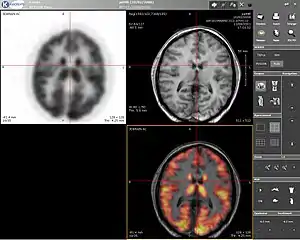

Positron emission tomography

Positron emission tomography (PET) is a nuclear medicine imaging technique which produces a three-dimensional image or picture of functional processes in the body. The theory behind PET is simple enough. First a molecule is tagged with a positron emitting isotope. These positrons annihilate with nearby electrons, emitting two 511 keV photons, directed 180 degrees apart in opposite directions. These photons are then detected by the scanner, which can estimate the density of positron annihilations in a specific area. When enough interactions and annihilations have occurred, the density of the original molecule may be measured in that area. Typical isotopes include 11